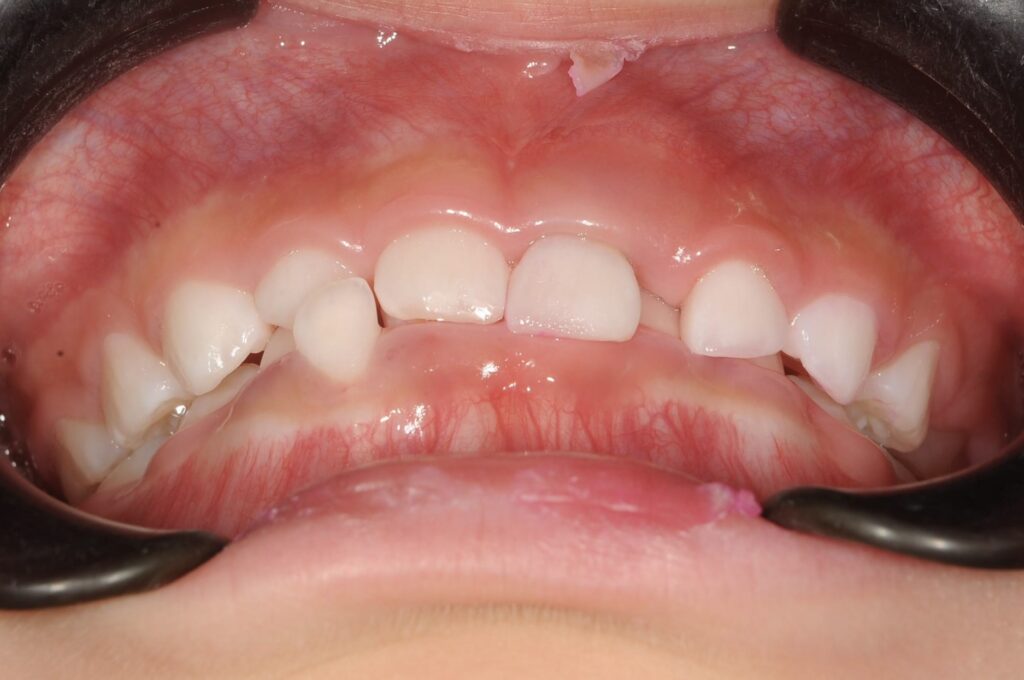

BEFORE

AFTER

主訴

右下の歯が飛び出ているので治したい。

診断名・主な症状

過蓋咬合

年齢

5歳

治療内容

上下の歯並びの幅を拡げつつ、前歯の関係を改善しました。

使用装置

急速拡大装置

リンガルアーチ

機能的矯正装置(マイオブレース)

抜歯部位

抜歯なし

治療期間

2年 + 後戻り止め期間(5年)

通院回数

25回

費用

50万円程度(税別)

リスク・副作用

痛み、歯肉退縮、歯根吸収、抜歯に伴う出血や腫れが生じることがあります。